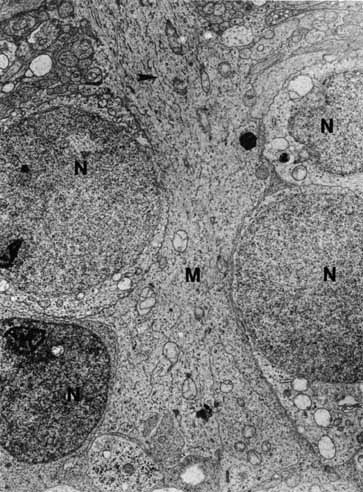

The cells within the retina can be divided into neuronal, glial, and vascular components. The neuronal cells are responsible for the primary function of the retina (i.e., conversion and transmission of incoming light into an electrical signal perceived by the brain). This is achieved through intricate synaptic connections among three different classes of retinal neurons, namely, photoreceptors, interneurons, and ganglion cells. A detailed understanding of the cellular morphology of these neuronal cells and their synaptic connections has been possible in recent years with the advent of electron microscopy, immunohistochemistry, and Golgi-impregnated preparations. Morphologically, 55 different types of retinal neurons have been identified in the mammalian retina to date. The function of 22 of these cell types is known. Each morphological type of retinal neuron appears to have a distinct physiological function. As further studies improve our understanding of the retina's role in processing the visual signal, the function of the remaining identified cell types will become apparent.

To appreciate the complexity of the interneuronal connections within the retina, an understanding of the basic morphology and function of synapses and other interneuronal junctions is important. The retinal neurons form three major types of intercellular connections: the chemical synapse for neuronal signal transmission, the zonula adherens that maintains tissue structure, and the gap junction that provides electrical transmission between developing retinal cells. These junctions have important morphologic similarities and differences that reflect their differences in function.

The synaptic junction of a typical chemical synapse consists of specialized apposed membranes of the two neuronal cells, separated by a 20- to 30-mm cleft.45 Similar to other intercellular junctions, such as zonulae adherentes, the plasma membrane of the synaptic junction contains tufts of fine filaments that insert into cytoplasmic densities, and the two apposing cell membranes are glued together by a thin, dark plate of filamentous material in the intercellular cleft.46 However, unlike the interepithelial cell adherence, the interneuronal synapse is polarized and has an asymmetric predominance of intracytoplasmic fibrils in the postsynaptic side of the junction.

The distinction between the morphology of the synaptic junction and that of the zonula adherens is important because both types of junctions are present between neuronal cells in the retina. These nonsynaptic junctions do not serve the purpose of electrical communication between cells. As in epithelial tissue, where they are commonly found, the zonulae adherentes act as binding sites to maintain tissue cohesion.45 In neural tissue they are usually short and have been given the special label puncta adhaerentia.46

Another type of junction between neuronal cells in the retina is the gap junction.47 In a gap junction, there is close apposition between presynaptic and postsynaptic membranes, and current is allowed to pass directly between adjacent cells. Thus, it is classified as an electrical synapse. Because no chemical mediator substance is involved, the rate of signal transmission is faster in these junctions than in typical chemical synapses. In some synapses, characteristics of both the chemical synapse and the gap junction are found. These connections, called “mixed synapses,” have not been found in the retina thus far.45

The electrical synapse (gap junction) characteristically shows a transsynaptic gap with a seven-layered structure produced by the approximation of membranes from the two juxtaposed cells (Fig. 19).48 The synapse consists of four dense lines and three intervening light spaces. It lacks the morphologic detail characteristic of the chemical synapse. Thus, they are localized best by tracer coupling. There are no vesicles and no obvious changes in the cytoplasm on the two sides of the junction. The gap junction does not function by the use of a chemical transmitter. Instead, it offers a low-resistance pathway between the cells. The extent of the electrical coupling of the adjacent cells appears to be dependent on the level of expression and type of the connecting particles (connexin). Thus, plasticity of the coupling in the retina is possible and the retina has the potential to optimize vision for the ambient lighting conditions.49

Fig. 19 Electron micrograph of a gap junction between two horizontal cells in a teleost retina. (Courtesy of Dr. Charles Zucker)

The close apposition of the plasma membranes of the gap junction allows for rapid and well-insulated electrical transmission to occur in either direction. Gap junctions have been identified between photoreceptor terminals, horizontal cells, and amacrine cells.50–54 In the vertebrate retina, gap junctions usually mediate lateral connections, coupling neurons of a single subtype into an extended array of mosaics in the plane of the retina (homologous).55 Occasionally, these electrical synapses can be seen between bipolar terminals and amacrine cells processes (heterologous).56,57 In these instances, they may play a role in transmitting signals from the photoreceptor to the ganglion cell.58 Based on biotinylated tracer studies, at least 3 different types of gap junctions have been found.59 The most permeable gap junctions were between A-type horizontal cells. The lowest permeability gap junctions were found between cone bipolar cells and AII amacrine cells. Intermediate range gap junctions were found between amacrine cells and between B-type horizontal cells.